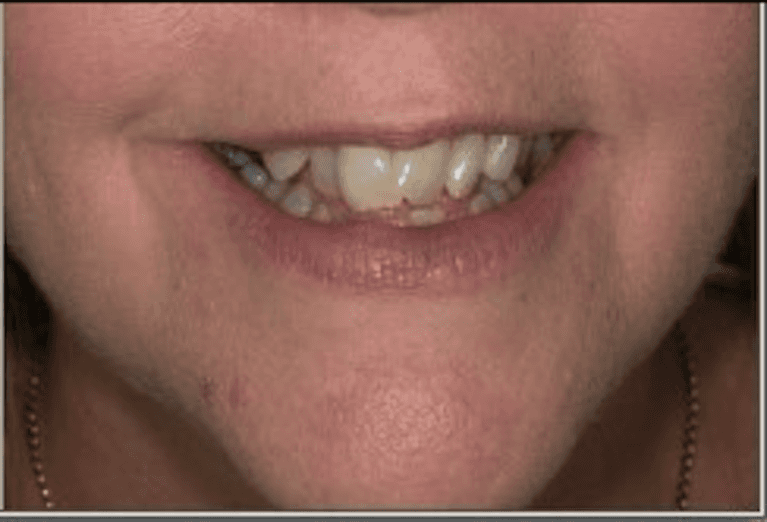

This patient came to Carewell Dental looking to address significant crowding and overlapping that had long affected her confidence. By utilizing a customized clear aligner treatment plan, we were able to gently guide her teeth into their ideal positions without the need for traditional metal braces. The result is a beautifully balanced, wider smile that not only improves her dental health but also perfectly complements her natural features. It’s a testament to how modern technology can deliver life-changing results right here in Rutland.